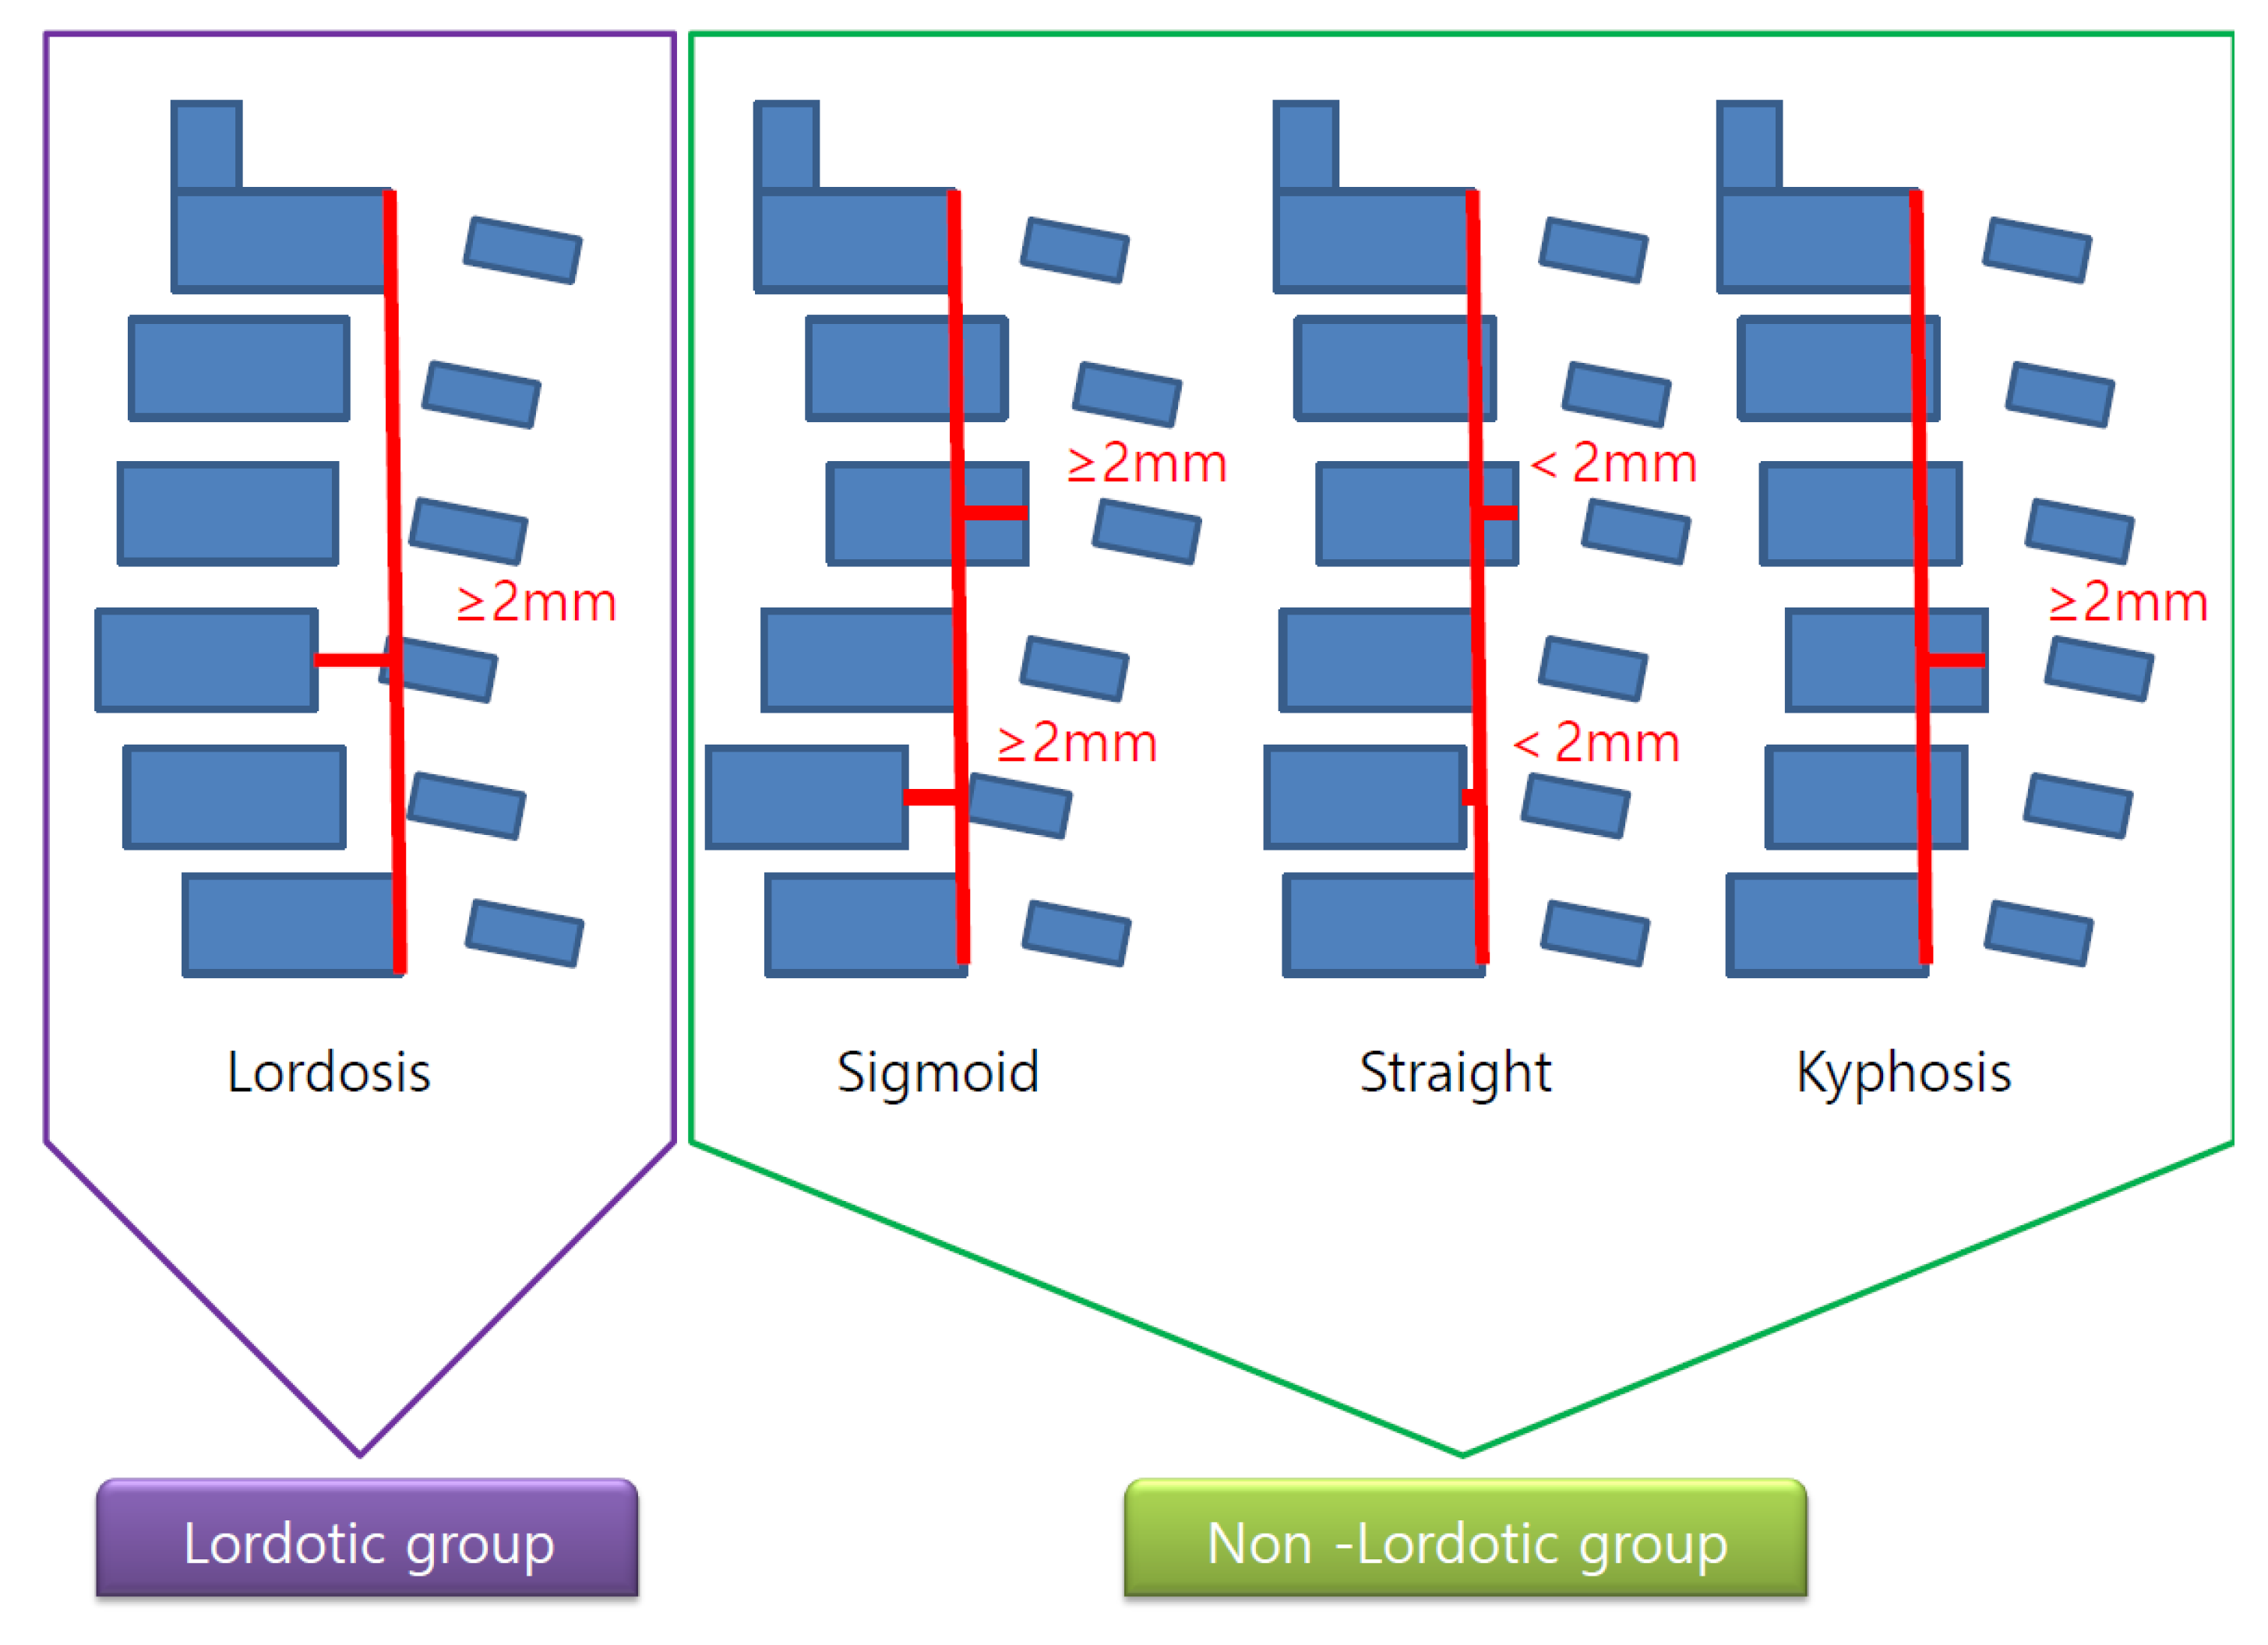

2.4. Radiological Analysis